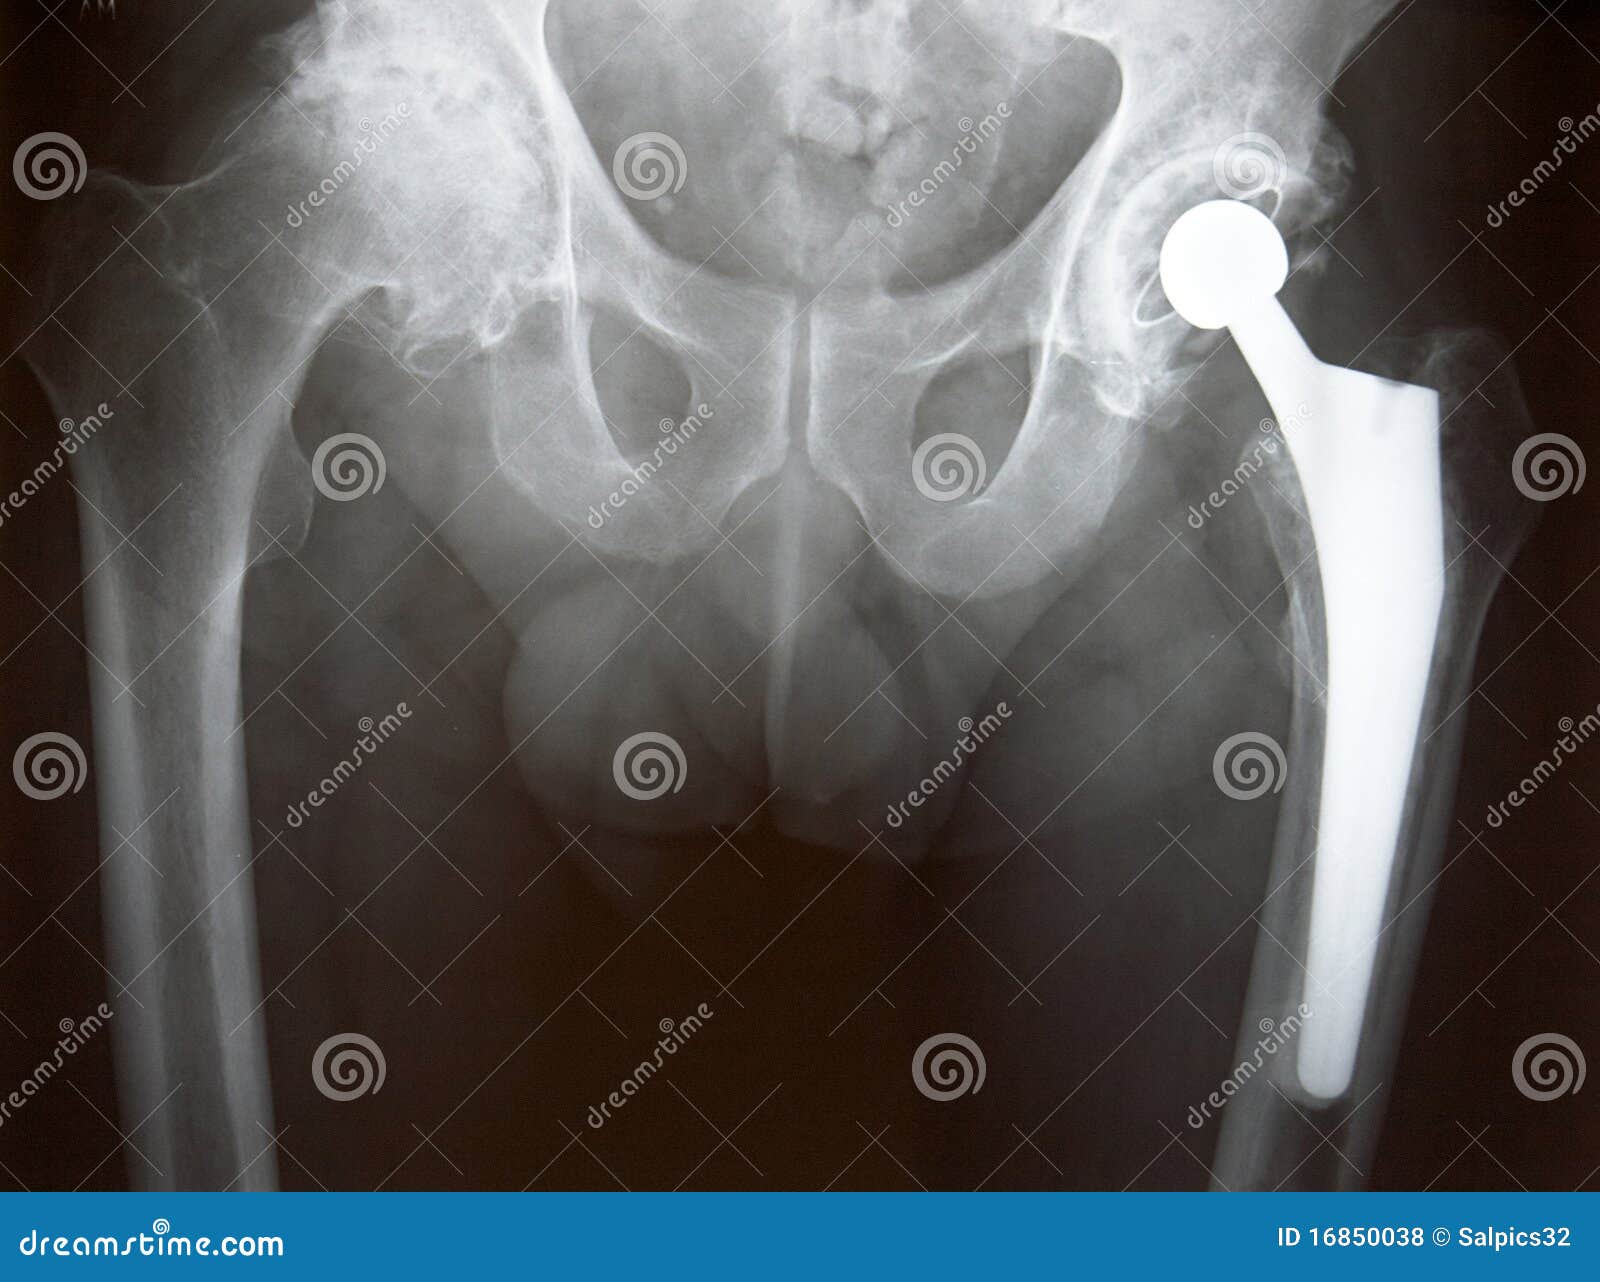

Xray of Hip Replacement stock photo. Image of replacement 16850038 Replacement Hip Xray in a hemiarthroplasty, also called partial hip replacement, the femoral head and neck are replaced. total hip replacement (thr), or total hip arthroplasty (tha), is a procedure that removes damaged bone and cartilage and. total hip arthroplasty (tha), also known as total hip replacement (thr), is an orthopedic procedure that involves the. radiography is the primary. Replacement Hip Xray.

Xray of Hip Replacement stock photo. Image of replacement 16850038 Replacement Hip Xray Your orthopaedic surgeon will remove the damaged cartilage and bone and then position new metal,. during hip replacement, a surgeon removes the damaged sections of the hip joint and replaces them with parts. radiography is the primary imaging method for the evaluation of total hip arthroplasty. in a hemiarthroplasty, also called partial hip replacement, the femoral head. Replacement Hip Xray.